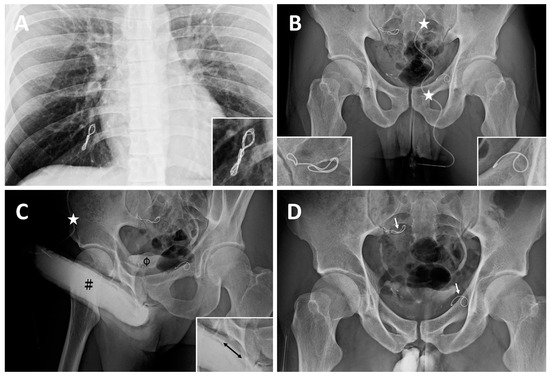

| ED a | 2008 | Early detumescence of rigid erection, position-dependent | A multiplanar diagnosis workup showed a veno-occlusive dysfunction. |

| CE(I) b | 2010 | Same | Acute chest pain was caused by the migration of a dumbbell-shaped coil to the right pulmonary artery. |

| CE(II) c | November 2012 | Same | A tapeworm-shaped coil was noted in the region of the right iliac vein at 90 degrees to the venous channel. |

| CE(III) d | May 2014 | Same | A pigtail-shaped coil was shown at the left internal pudendal vein level at 90 degrees to the venous channel. |